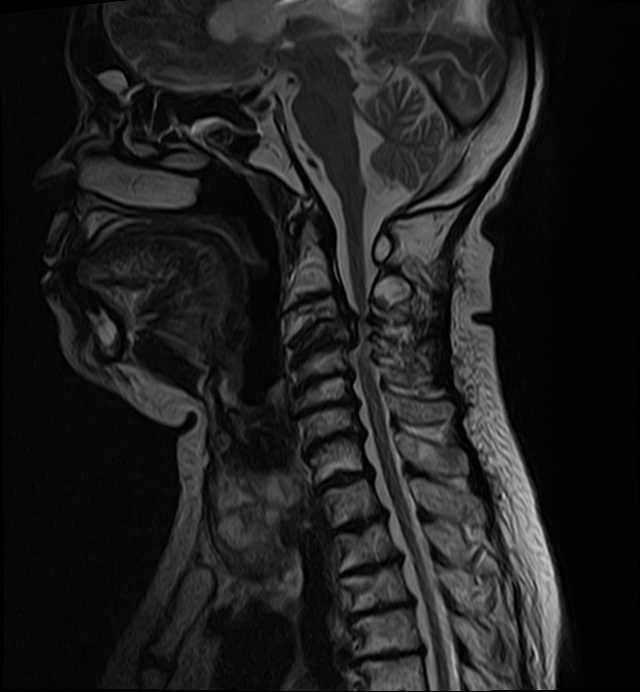

Mr John had this problem and did an MRI scan. This is the gold standard test for cervical myelopathy. Ordinary x-rays can show the bones that are wobbly but MRI scan shows how the spinal cord is being affected and where. The pressure and damage to the spinal cord was evident in Mr John. However, the pressure was from the front and back of the neck.